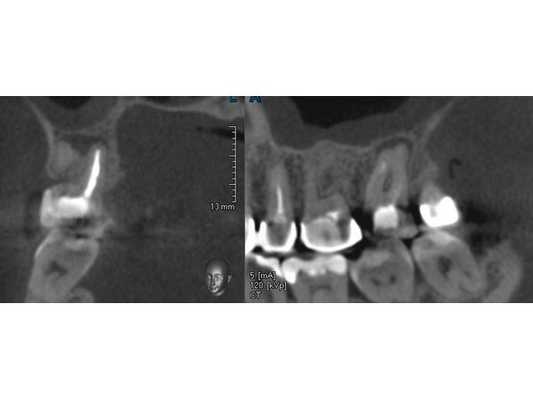

В поликлинике "Наша Клиника-Дент" проведено визиографическое обследование свищевого хода, предварительно в него был введён гуттаперчевый штифт для уточнения локализации воспалительного процесса. Выявлен очаг воспаления в области корней 17 зуба. Также обнаружен участок повышенной плотности, по конфигурации соответствующий фрагменту инструмента в мезиально-щёчном корне 16 зуба.

После протезирования временной коронкой пациентка не предъявляла жалоб. На контрольной томограмме в сентябре 2019 года наблюдается уменьшение очага деструкции, восстановление дна гайморовой пазухи. Рекомендовано обратиться к врачу-ортопеду для протезирования постоянной ортопедической конструкцией. Осмотр в марте 2020 года.